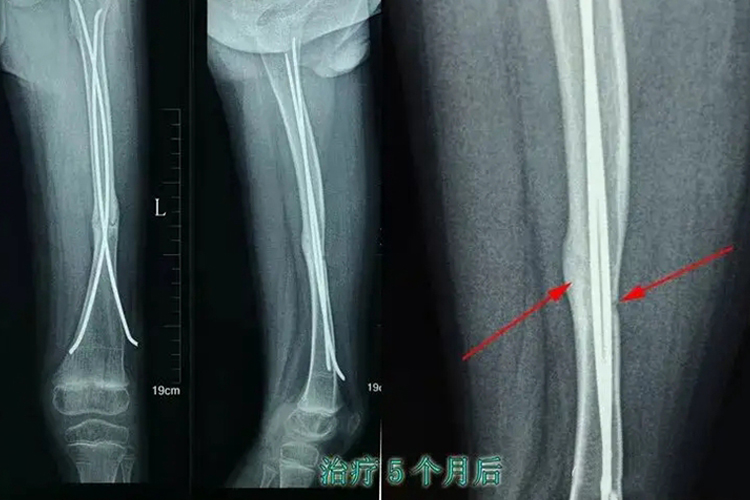

骨折愈合则是发生骨折的部分重新恢复连续的过程,包括局部无压痛及纵向叩击痛局部无异常活动X线平片显示骨折处有连续性骨痂骨折线模糊等临床标准骨折愈合是一个复杂而连续的过程,一般可以分为三个阶段血肿炎症机化期骨折后,骨髓腔骨膜下和周围组织血管会发生破裂出血,形成血肿之后,凝血。